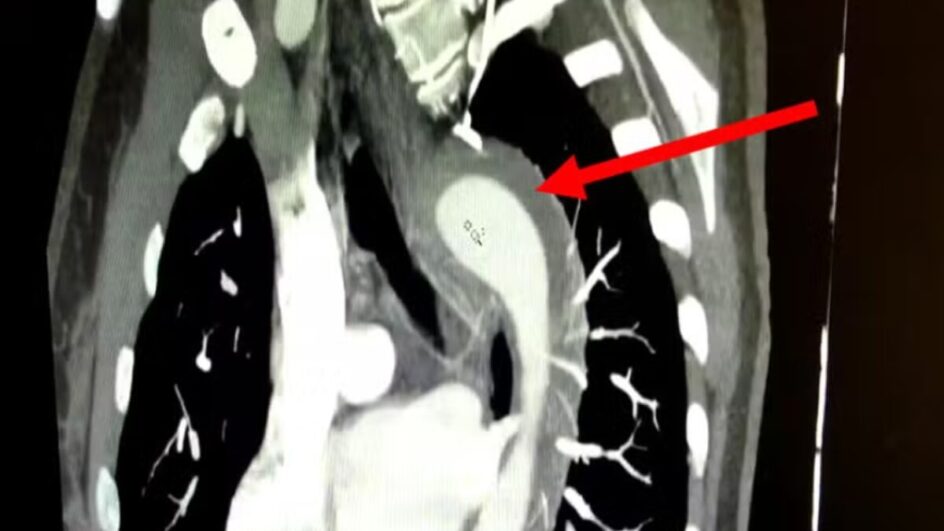

Imagem da artéria publicada na revista (Foto: American Journal of Case Reports, Divulgação)

A paciente tinha hipertensão não tratada há um ano e tabagismo há 17 anos. Para entender o que aconteceu, ela passou por exames de imagem que indicaram hematoma intramural na aorta, uma condição grave que envolve o sangramento na parede da aorta.

O quadro é considerado uma Síndrome Aórtica Aguda (SAA) e, se não tratado adequadamente, pode evoluir para aneurisma ou ruptura aórtica total, com risco de morte. A atividade sexual é considerada um esforço físico moderado, mas pode alcançar níveis de exercício quase máximos. No entanto, ainda assim, a associação da atividade com aumento do risco de SAA e morte súbita é rara.